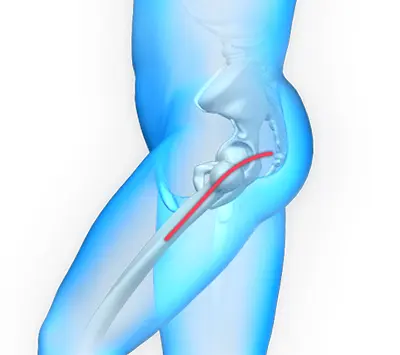

Posterior Approach

Posterior hip replacement is a minimally invasive hip surgery performed to replace the hip joint. It is also referred to as muscle-sparing surgery because no muscles are cut to access the hip joint, enabling a quicker return to normal activity.

In posterior hip replacement, the surgeon makes the incision at the back of the hip, close to the buttocks. The incision is placed so the abductor muscles, the major walking muscles, are not cut.

- An incision is made close to the buttocks beyond the abductor muscles.

- The surgeon separates the muscles and tendons to access the hip joint.